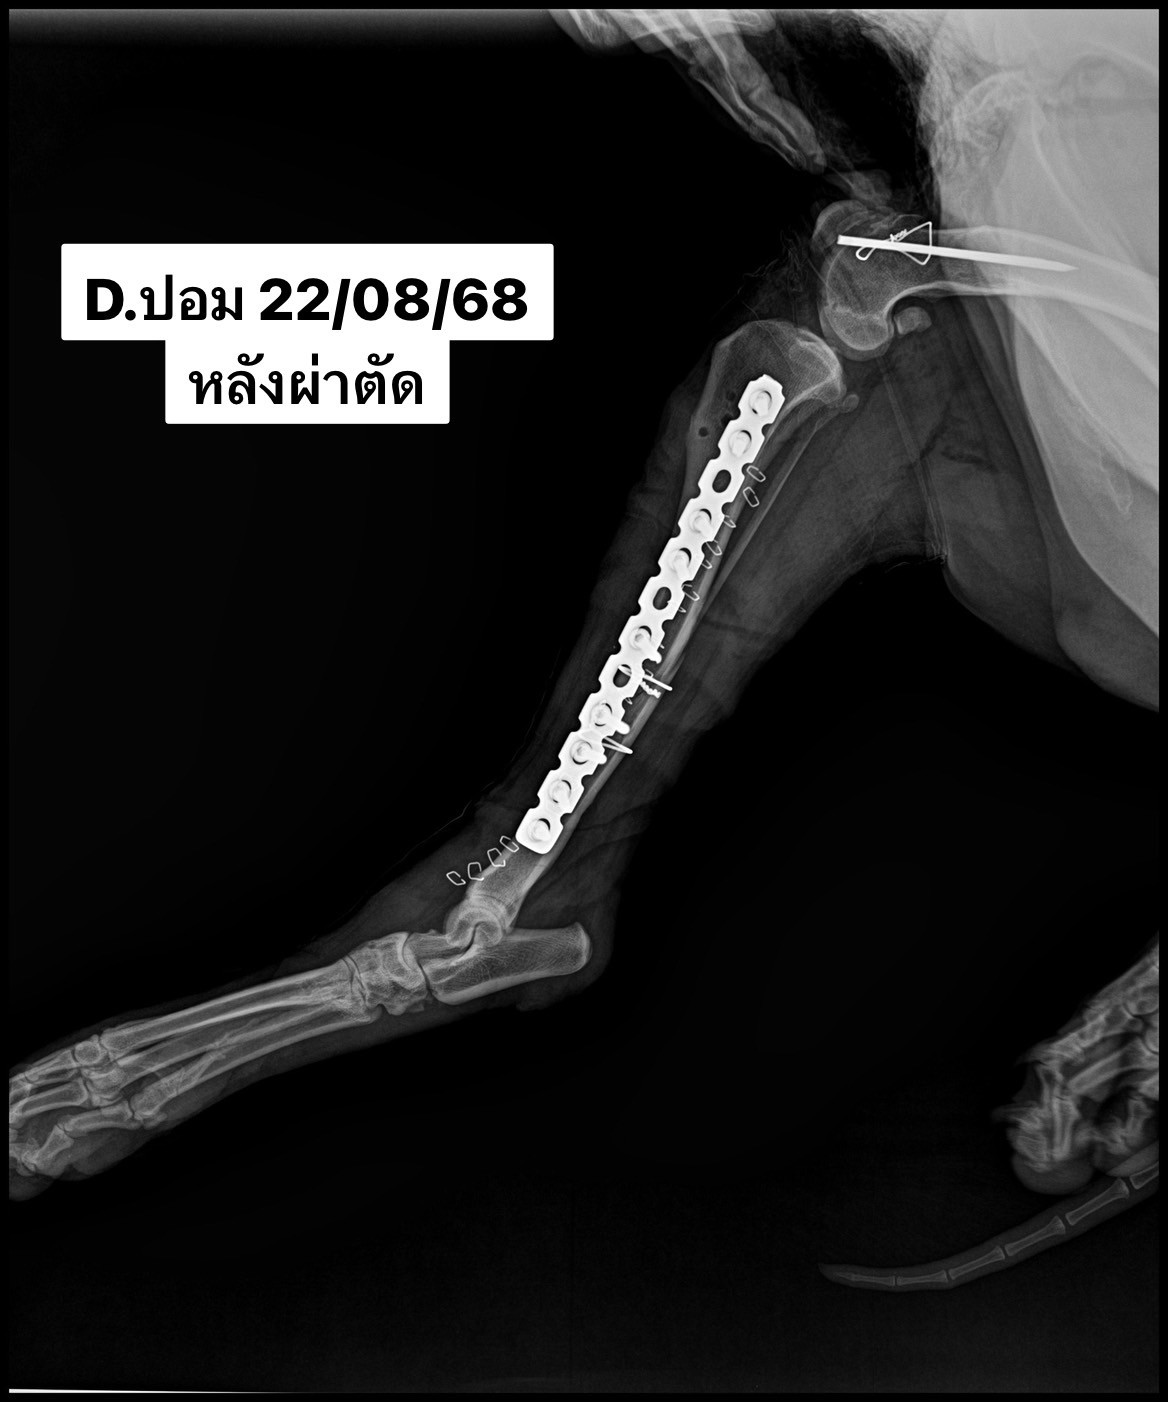

สัตวแพทย์จึงวางแผนการรักษาด้วยการ ผ่าตัดใส่แผ่นเหล็กตรึงกระดูกและมัดลวดพิเศษทางการสัตวแพทย์ (medial plate and cerclage wire) เพื่อให้กระดูกยึดติดแน่นในแนวที่ถูกต้อง ช่วยให้น้องปอมสามารถฟื้นตัวและกลับมาใช้ขาได้ตามปกติในอนาคต